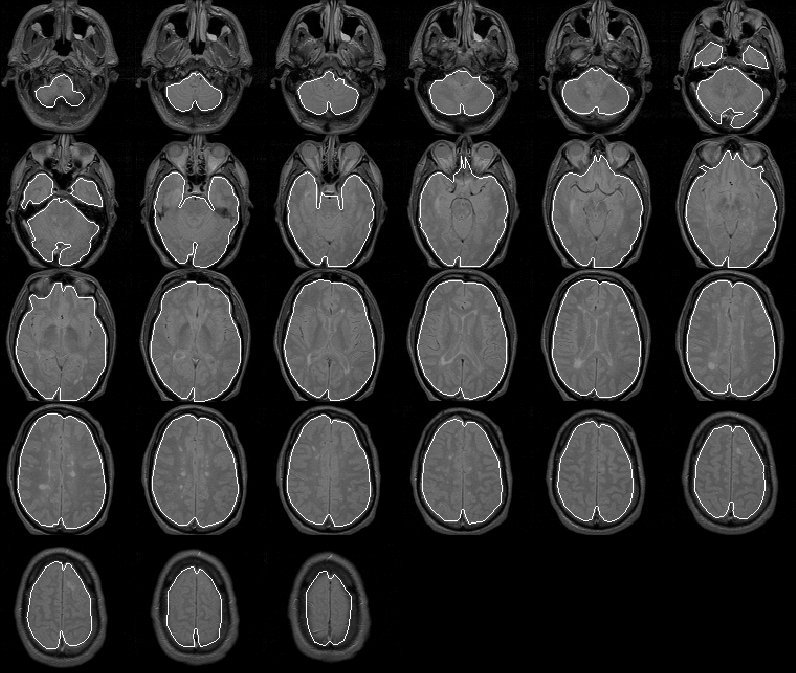

Figure 8.17: The final brain mask for MRI Data Set 1 overlaid on the PD-weighted scan.

The intracranial boundary defined by the final brain mask of Data Set 1 is overlaid on the PD-weighted MR volume in Figure 8.17. The mask outlines the brain remarkably well in all slices. Figure 8.18 shows slice 13 at a higher resolution. Notice that the final mask covers the entire brain, whereas the initial mask lies inside the brain.

Only slight errors occur in the first slice and some slices containing the eyes. In these slices, the brain mask excludes some very low intensity brain tissue. The errors are understandable since these low intensity tissues appear very similare to the intracranial cavity tissues.